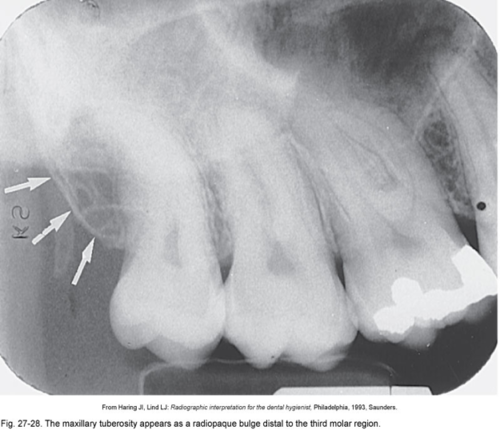

Maxillary tuberosity

Is the rounded end of the alveolar process of the maxilla

Coronoid process

Anterosuperior portion of the ramus

Seen when the patient’s mouth is open on posterior maxillary PA’s